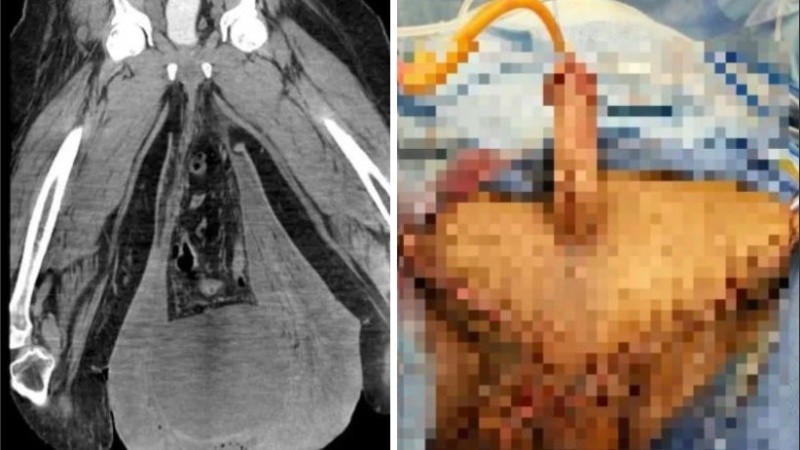

Cuando le realizaron un examen, este indicó que la piel estaba engrosada, de color rojo intenso y con dos heridas abiertas e infectadas. En tanto, las exploraciones mostraron una hernia inguinal.

Durante los siguientes cinco días, el hombre permaneció en el hospital con antibióticos por vía intravenosa. El hidrocele, el término médico para el tipo de hinchazón en el escroto, mide 30,2 cm x 24,4 cm x 13,1 cm de tamaño. Los cirujanos plásticos cosieron el área del escroto del hombre con un injerto hecho de malla.